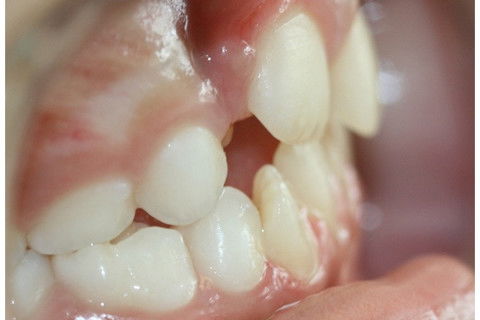

Ao exame clínico observou-se persistência do dente decíduo e erupção ectópica por palatina do sucessor permanente.

Foi realizada a exodontia do dente 51. Observa-se o dente 11 irrompendo por palatina, necessitando de tratamento ortodôntico.

Aguardou-se 3 semanas para que o dente 11 erupcionasse, e então foi instalado o aparelho com o helicóide a fim de descruzar o dente 11. Observou-se também, mordida cruzada posterior e ausência de espaço para os dentes 12 e 22, necessitando de encaminhamento para continuidade no tratamento ortodôntico.